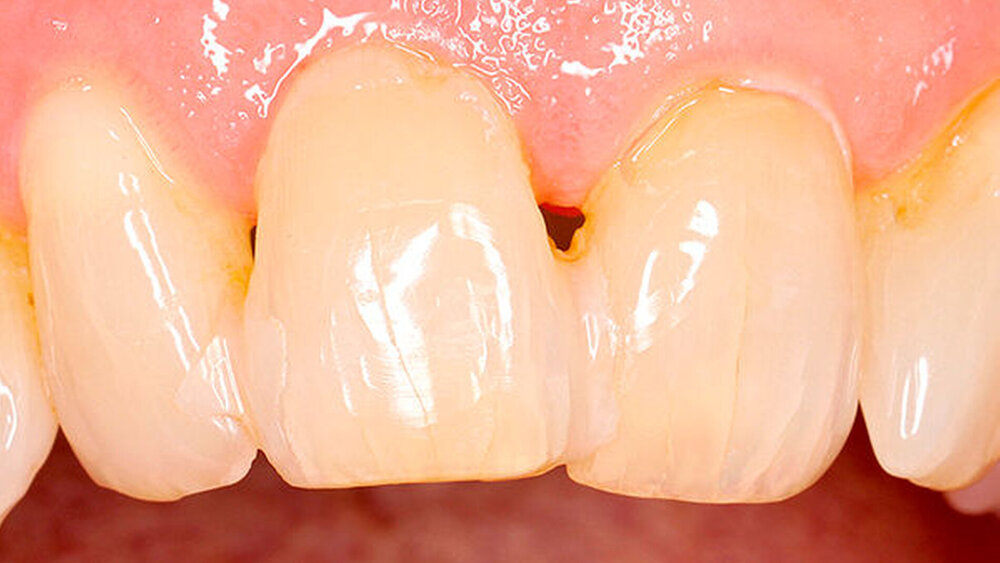

Sind dann auch eher Sofortversorgungsprotkolle umzusetzen?Hermann:Die erzielte Primärstabilität ist in den meisten Fällen so hoch, dass eine sofortige provisorische Versorgung/Belastung möglich ist. Somit können wir unseren Patienten effiziente Behandlungsabläufe anbieten. Die Effizienz zeigt sich beispielsweise auch bei der Reduktion der Bohrschritte durch ein flexibles Bohrprotokoll. Gerade im weichen Knochen benötigen wir meist nur drei Bohrschritte bis zur Insertion des Implantats und erzielten eine exzellente Primärstabilität durch eine geringere Aufbereitung des Implantatbetts. Auf den zusätzlichen Einsatz nicht-ablativer Techniken (Osteotome) kann häufig verzichtet werden. Ein Teil der 80 von uns gesetzten PROGRES ‧ SIVE- ‧ LINE Implantate befindet sich bereits in der prothetischen Nachkontrolle. Das klinische und prothetische Outcome ist hervorragend. Es gibt weder chirurgische Komplikationen noch Probleme bei der Einheilung, und die prothetische Versorgung funktioniert perfekt.

Ihr Fazit? Hermann:Zusammenfassend kann ich sagen, dass wir mit der CAMLOG PROGRESSIVE-LINE eine Erweiterung der klinischen Indikationen in Bezug auf eine simultane Vorgehensweise (Implantation und Augmentation kombiniert) beobachtet haben, und zwar aufgrund der bereits erwähnten Primärstabilität bei schwierigen anatomischen Situationen. So können wir in vielen Fällen auch eine Sofortversorgung/Sofortbelastung des Implantats in Erwägung ziehen. Die situative Adaptation des Bohrprotokolls verschafft uns eine effiziente Insertion, die vorhandene, bewährte Prothetikschnittstelle der Implantate von CAMLOG das vertraute Handling, und dies alles bei einem Implantat, das wir bei allen klinischen Situationen zum Einsatz bringen konnten.